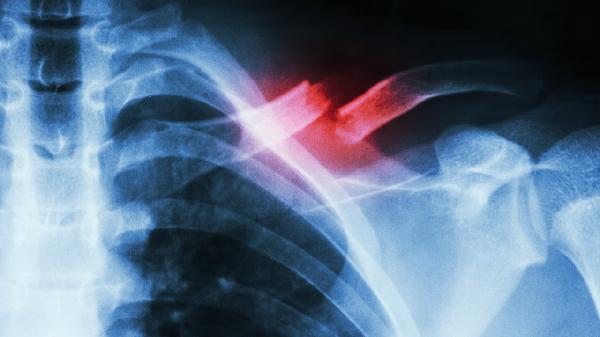

锁骨骨折的手术治疗方法主要有切开复位内固定术、髓内钉固定术、外固定支架固定术、微创钢板内固定术、关节镜下复位固定术。

适用于明显移位或粉碎性骨折。通过手术切口暴露骨折端,使用钢板螺钉系统进行固定。该方法能实现解剖复位,稳定性好,但创伤较大,术后可能遗留疤痕。术后需配合支具保护,定期复查X线观察骨折愈合情况。